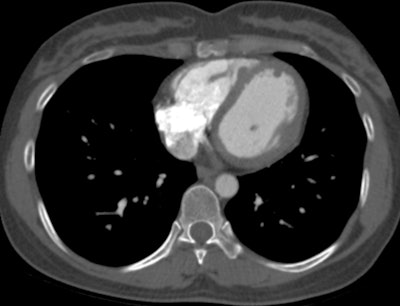

"Chest CT demonstrates poor sensitivity for detection of cardiac metastasis, with cardiac MRI performing much better. Still, neither CT nor MRI is as sensitive as [gallium-68 (Ga-68)] DOTATATE PET/CT for detection of neuroendocrine cardiac metastasis," noted Dr. John Renfrew and colleagues from the Mayo Clinic in Phoenix, Arizona, U.S.

The group evaluated the prevalence, distribution pattern, and radiotracer uptake characteristics of cardiac metastasis on Ga-68 DOTATATE PET/CT. On PET images, they documented and analyzed the maximum standardized uptake value of the cardiac metastasis and left ventricular chamber (blood pool), the Krenning score of the cardiac metastasis, and the presence of multisystem metastasis. They performed correlation with diagnostic CT and/or cardiac MRI to confirm the location of metastasis in the heart.

Of the 26 cases, 17 also underwent a contemporaneous chest CT exam. Only one of these CT scans demonstrated evidence of neuroendocrine cardiac metastasis, Renfrew and colleagues reported.